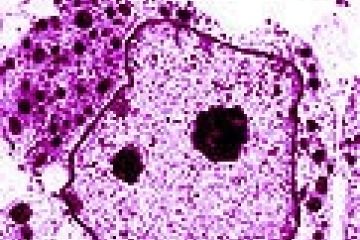

The freezing and thawing of human embryos can double or even triple the number of chromosomes in living cells, with potentially serious consequences for unborn offspring. The process was observed in...